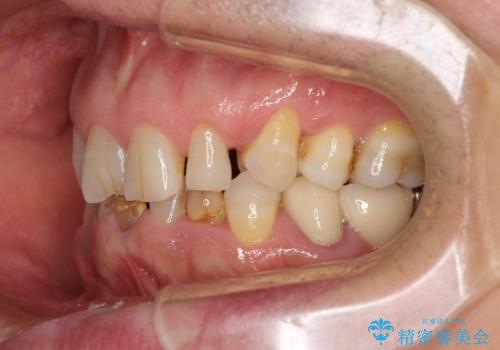

- 乳歯や矮小歯が多くある前歯部の審美障害が気にして来院された患者様です。

上顎の矮小歯は隙間が多く、歯軸の傾斜も大きかったため、部分矯正により補綴治療前に歯の位置を整えることとしました。

下顎の乳歯は支台歯として機能することは困難と思われたので、事前に抜歯をし、上顎の矯正治療終了のタイミングに合わせて、セラミックブリッジにて補綴治療することとしました。

前歯部はディープバイトという、上顎前歯が下顎前歯に深く覆い被さる咬合であったので、理想的には全顎矯正が必要となりますが、今回は患者希望により前歯部のみの部分矯正で対応しました。そのため下顎犬歯の神経を取り除くことになってしまったのは心残りであります。